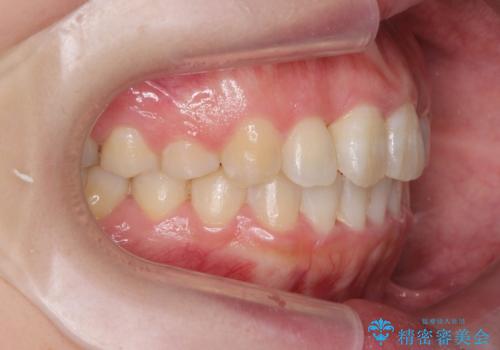

- 前歯のねじれを改善したい、と矯正治療を希望され来院されました。

上下の歯のがたつきを改善するマウスピース矯正治療と、下顎に見られる大きな骨隆起を外科的に除去する治療計画を進めていきます。

歯並びが改善したとともに、骨隆起を除去したことで舌をしまうスペースも増え安定した口腔内環境を確立することができました。